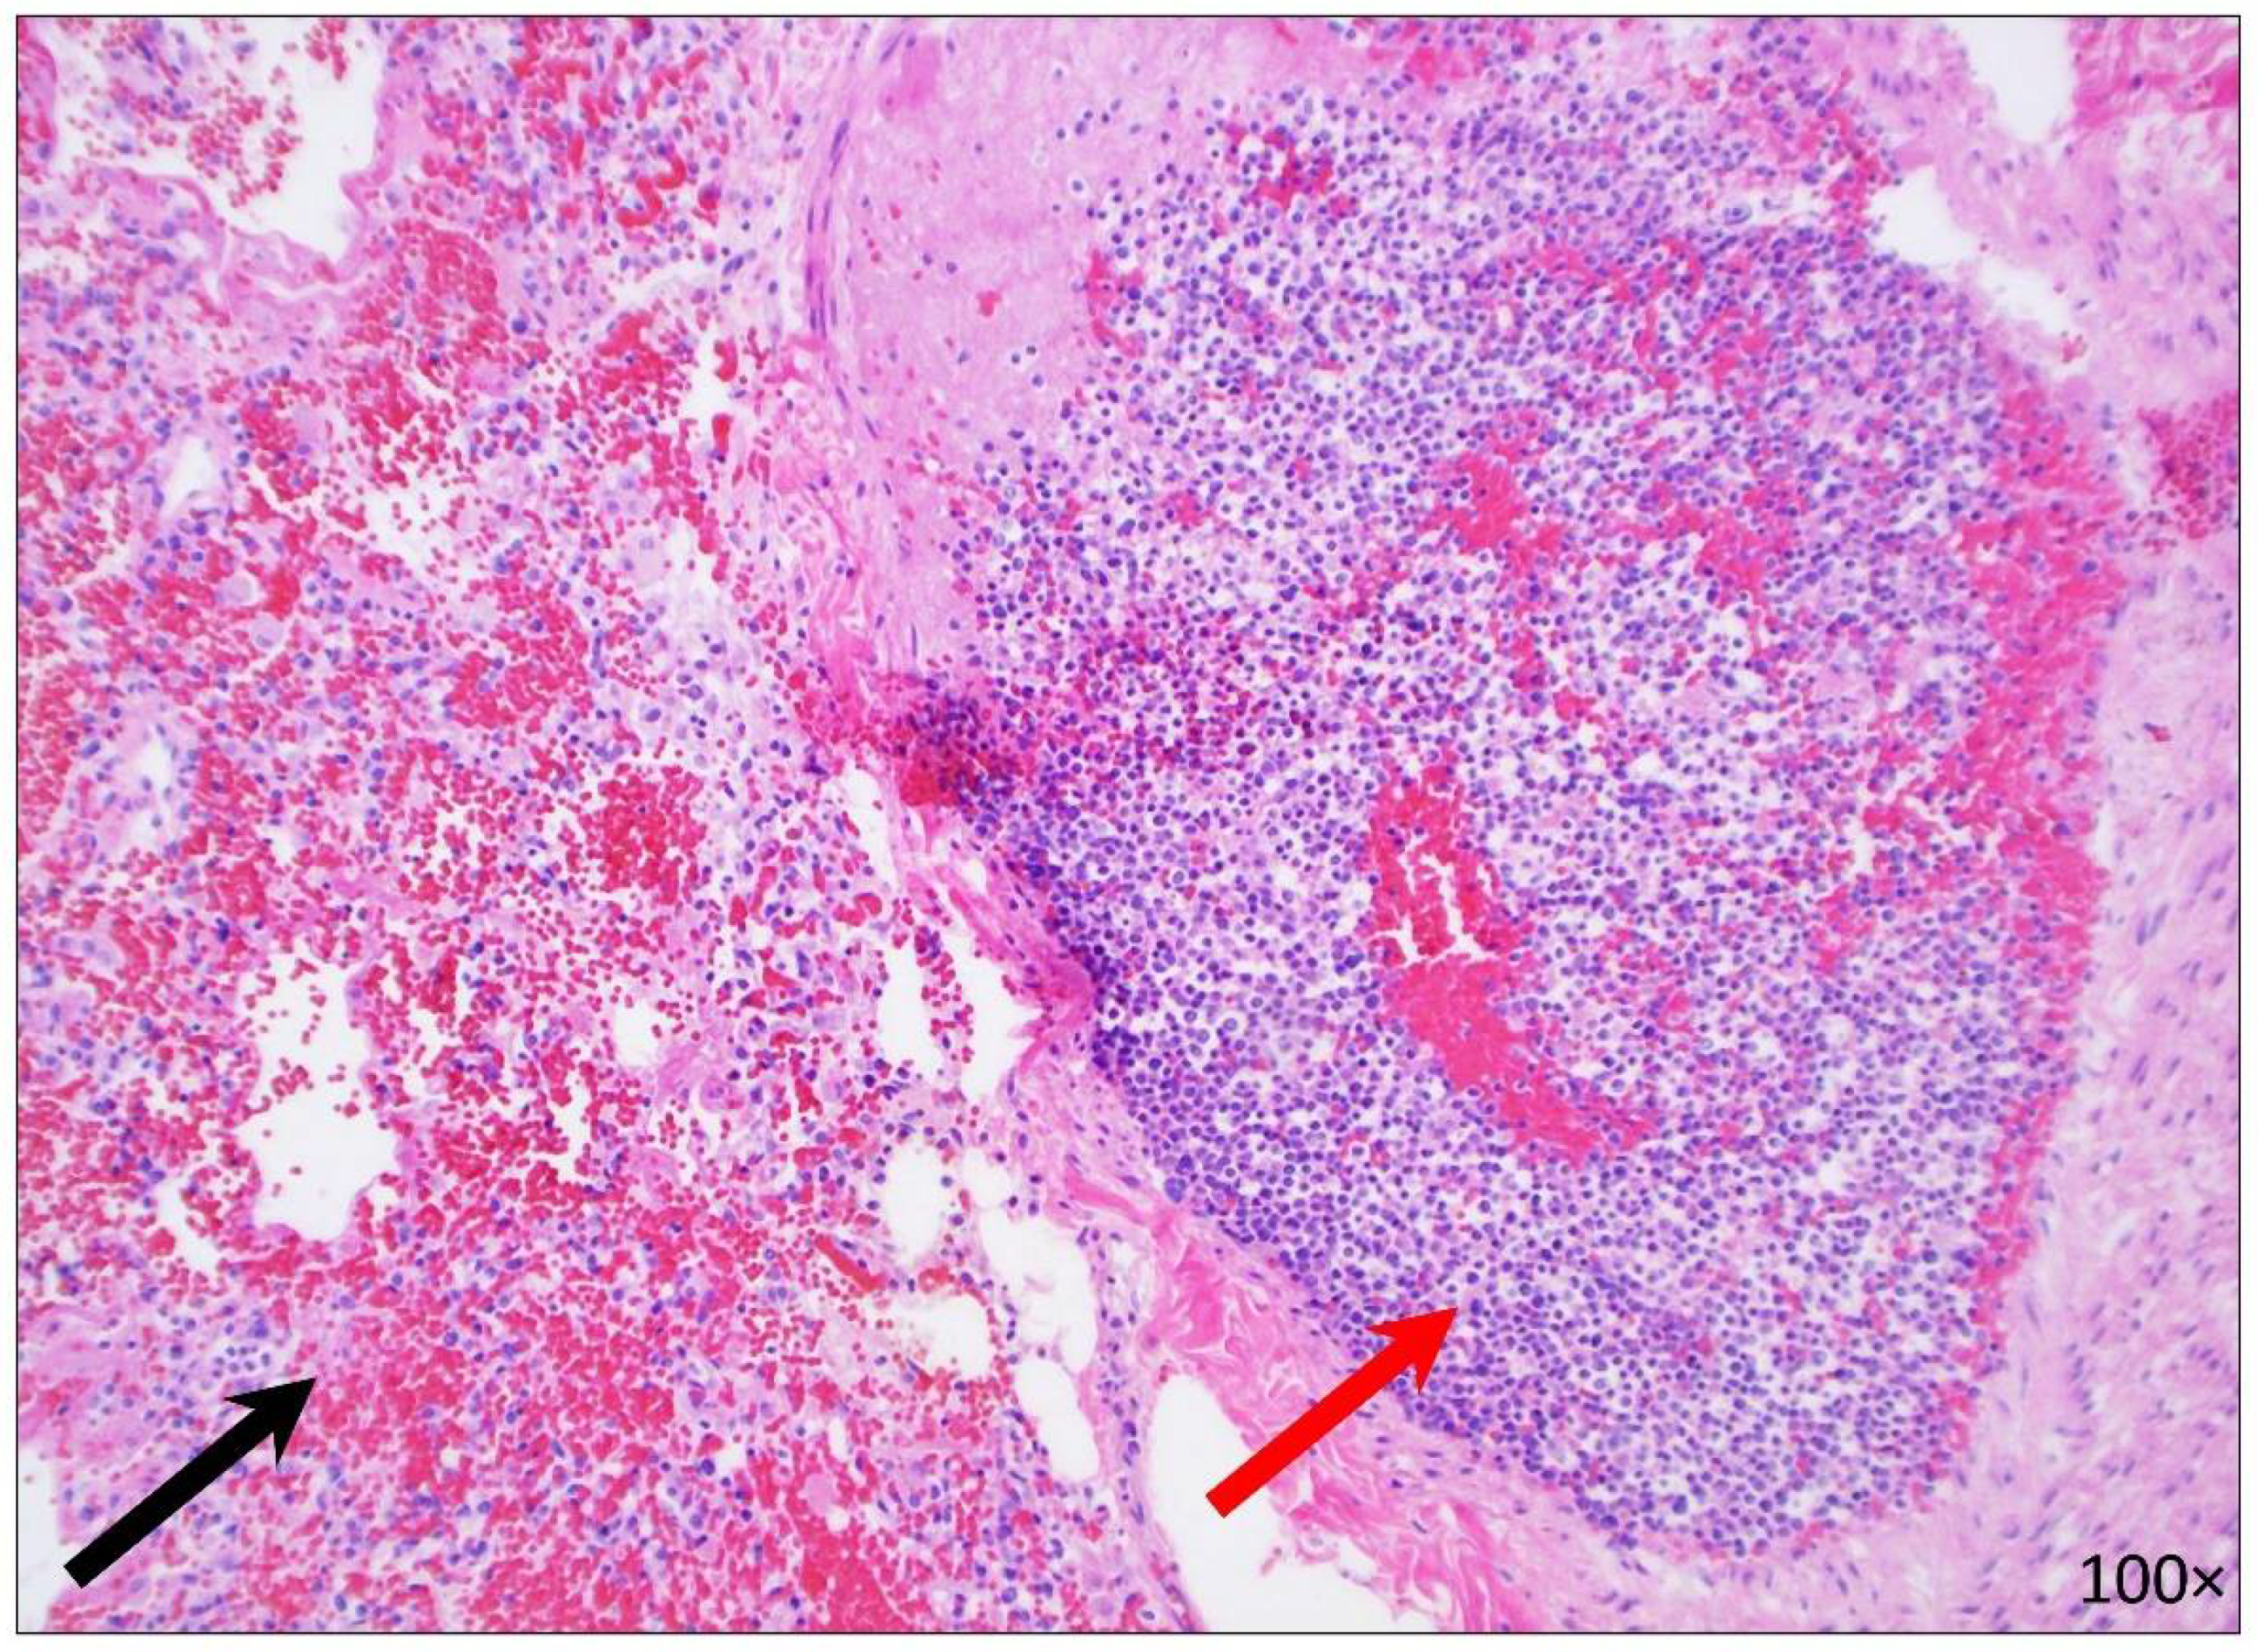

2.2.5. Hematopoietic System

2.2.7. Central Nervous System